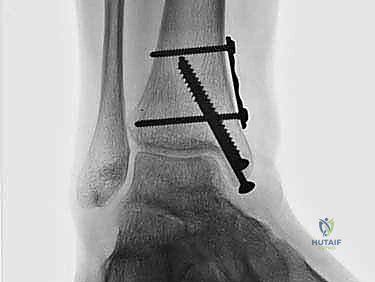

2. الزرع الغضروفي العظمي الذاتي (OATS / Autograft): وهو محور حديثنا والتقنية الذهبية التي يبدع فيها الأستاذ الدكتور محمد هطيف لعلاج الآفات المتوسطة والكبيرة.

الغوص العميق: تقنية الزرع الغضروفي العظمي الذاتي (OATS) خطوة بخطوة

تُعد تقنية OATS (Osteochondral Autograft Transfer System) بمثابة "زراعة أعضاء دقيقة" داخل المفصل. الفكرة الأساسية هي أخذ أسطوانة صغيرة من العظم والغضروف السليم من منطقة لا تحمل وزناً كبيراً في جسم المريض (غالباً من مفصل الركبة)، ونقلها وزرعها في مكان الآفة التالفة في الكاحل.

هذه التقنية توفر "غضروفاً زجاجياً حقيقياً" (Hyaline Cartilage)، وهو نفس نوع الغضروف الأصلي الذي خُلق به الإنسان، مما يضمن متانة وقدرة على تحمل الأوزان لا يوفرها أي علاج آخر.